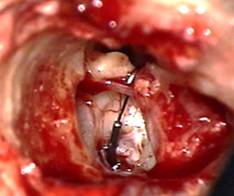

Figura 13. Maleoestapedotomía |

Figura 14. |

Presente en el 0,6 al 6% de los pacientes. Cuando se presenta, se realiza una resección de la cabeza y se aplica una prótesis que va desde el mango del martillo a la platina, lo que se le conoce como maleoestapedectomía (Fig.12-13).